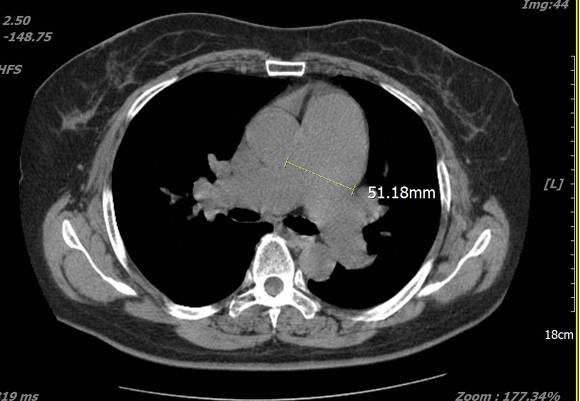

pic 8. main Pulmonary Artery - 51mm

pic 9. lung CT ( pulmonary artery size - 51mm)